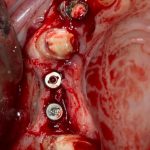

ну, или как-то так:

При этом, я хотел бы обратить ваше внимание на один важный момент. То, с чем вы сейчас работаете — не кость, в привычном нам гистолого-физиологическом понимании. Это костная мозоль вперемежку с графтом. Её свойства довольно сильно отличаются от того, что мы привыкли называть костной тканью. Поэтому при установке имплантатов соблюдайте максимальную осторожность и щадящий режим. Никаких диких торков, усилий, больших переходов между размерами фрез допускать нельзя. Будьте аккуратны.

Иначе, кривокосячной имплантацией вы можете испортить даже мастерски проведенную остеопластическую операцию.